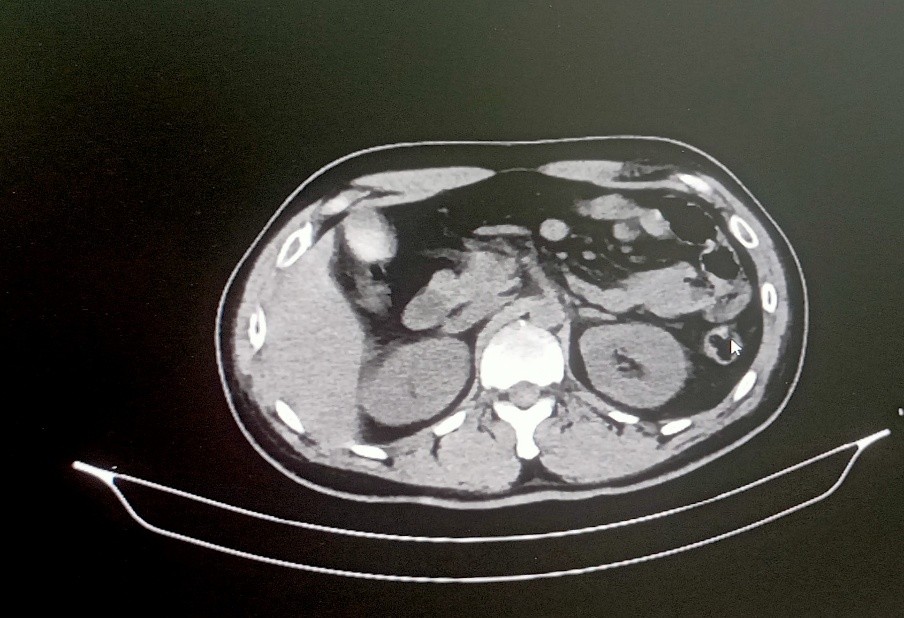

Multislice CT lower peripheral angiogram – Report 19.06.2025

Thrombosis in the distal external iliac artery on right side with partial luminal narrowing with normal opacification of common femoral artery, superficial femoral artery up to the middle 1/3RD with thrombus causing complete occlusion with non – visualization of the arteries distal to it. The left lower limb artery shows normal opacification.

Right lower limb – Arterial study 19.06.2025

Echogenic thrombus in right CFA causing partial luminal occlusion